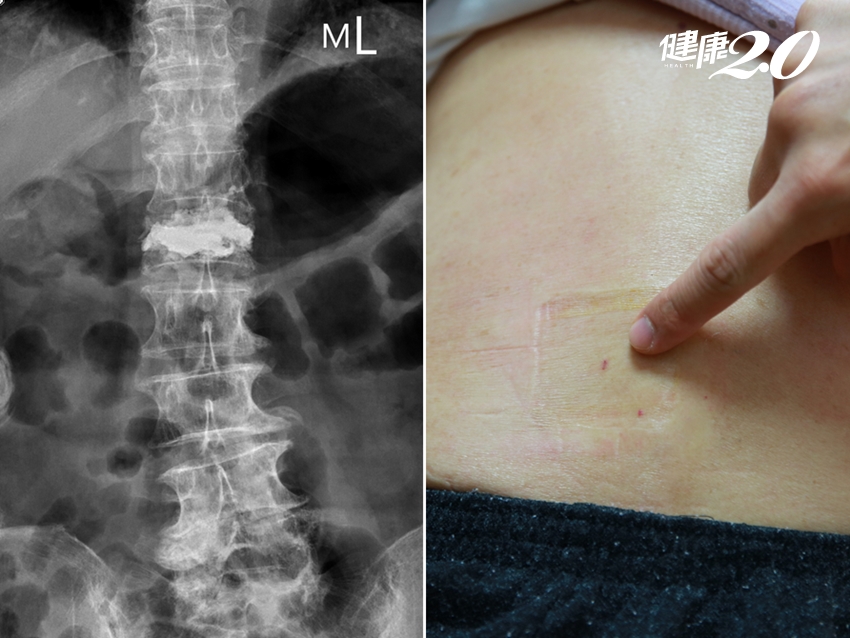

▲ 術後陳阿嬤脊椎X光攝影(左圖);手術傷口小,約只有一個針頭大小(右圖)。